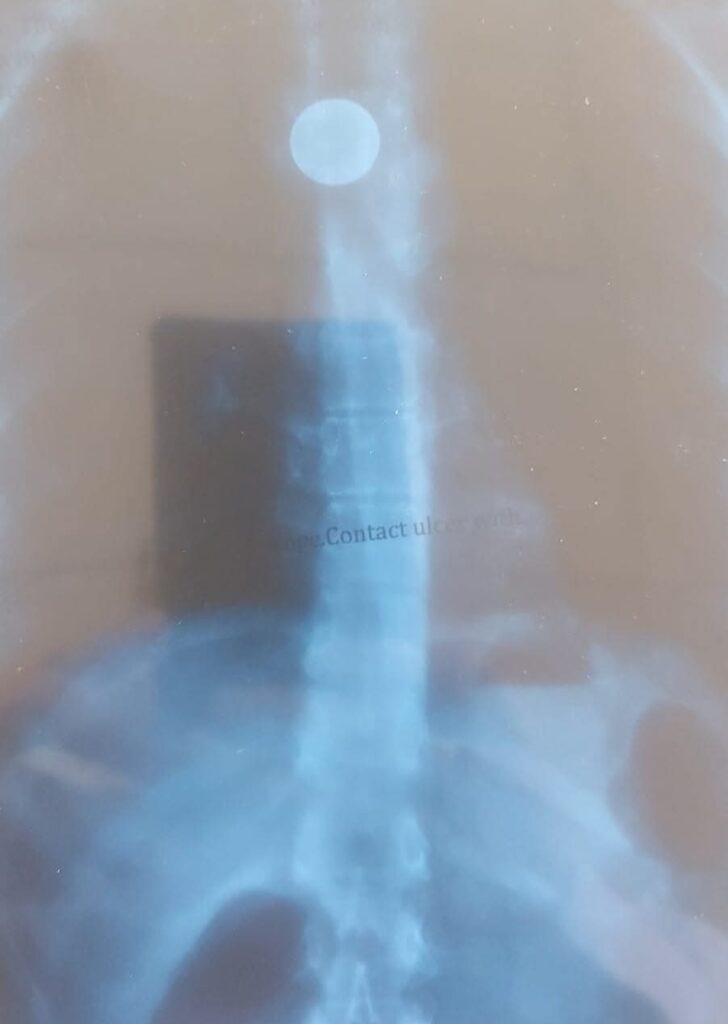

लाइव हिमाचल/शिमला: AIMSS चमियाना के गैस्ट्रोएंटेरोलॉजी विभाग की टीम ने एक बेहद जटिल और दुर्लभ केस में एक बड़ी सफलता हासिल की है। विभाग के डॉ. बृज शर्मा, डॉ. राजेश शर्मा, डॉ. विशाल बोध और डॉ. आशीष चौहान की टीम ने 23 वर्षीय युवती के भोजन नली फूड पाइप में फंसे सिक्के को सफलतापूर्वक निकालने में कामयाबी पाई है।जानकारी के अनुसार, मरीज पिछले कई वर्षों से निगलने में कठिनाई की समस्या से जूझ रही थी। उसने कई अस्पतालों में इलाज कराया, लेकिन असली कारण का पता नहीं चल पाया। जांच के दौरान यह सामने आया कि युवती ने लगभग 15 वर्ष पहले, जब वह दूसरी कक्षा में थी, गलती से एक सिक्का निगल लिया था, जो भोजन नली में फंसा रह गया था। पहले भी सिक्का निकालने के कई प्रयास असफल रहे थे, लेकिन AIMSS चमियाना की गैस्ट्रोएंटेरोलॉजी टीम ने आधुनिक एंडोस्कोपिक तकनीक की मदद से सिक्का सुरक्षित रूप से बाहर निकाल लिया। ऑपरेशन पूरी तरह सफल रहा और मरीज अब पूरी तरह स्थिर है।चिकित्सक दल ने बताया कि इतने लंबे समय तक भोजन नली में धातु का फंसा रहना बेहद दुर्लभ मामला है, और इसका सफल उपचार चिकित्सा दृष्टि से बड़ी उपलब्धि है।